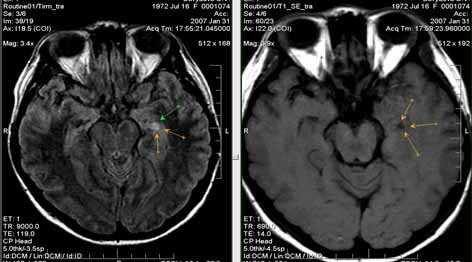

5. МР-картина узловой субкортикальной гетеротопии левой лобно-теменной области.

В первом случае визуализируются узлы гетеротопии в субкортикальных отделах белого вещества парасагиттальных отделов левой лобно-теменной области.

На втором скане - единичный мелкий узел гетеротопии в белом веществе правой лобной доли (характеристики МР-сигнала идентичны серому веществу головного мозга)

На третьем изображении - множественные узлы гетеротопии вдоль стенок переднего рога левого бокового желудочка и задних рогов обоих желудочков (характеристики МР-сигнала узлов идентичны серому веществу головного мозга)

6. МР-картина перестройки серого вещества правой лобной доли (характерно для фокальной кортикальной дисплазии).

Участок перестройки структуры серого вещества правой средней лобной извилины с утолщением серого вещества и визуализацией дополнительных мелких извилин и участков линейного глиоза.